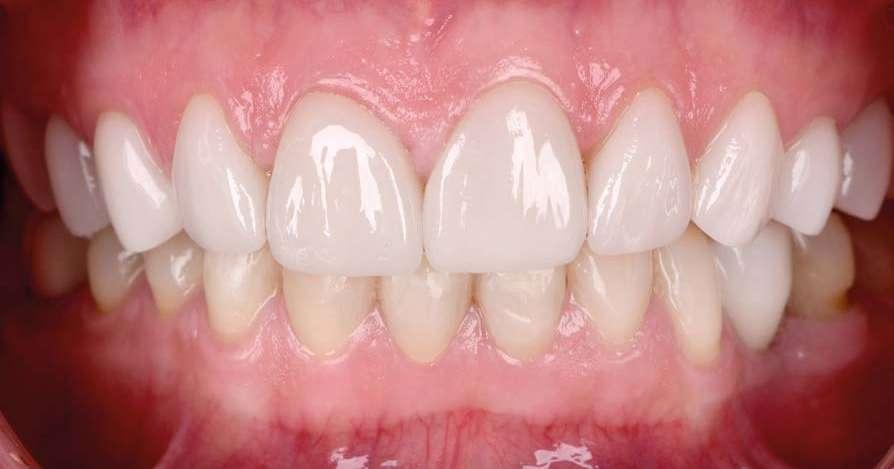

En la arcada superior por el contrario se decidió poner unas carillas de disilicato para poder cubrir las expectativas de la paciente y ajustar el color al que ella deseaba, bajando casi en 5 tonos el color final. Se planificaron preparaciones digitales conservadoras.

La tecnología digital permite lograr el equilibrio de espesores ideal para cada caso, así como un eje de inserción adecuado. Todo esto permite dar una garantía de longevidad a las restauraciones planificadas.

En este caso se realizó una preparación previa a la preparación guiada en los márgenes y zonas interproximales, para camuflar el sustrato y dar una correcta inserción; y posteriormente se utilizaron unas guías de tallado diseñadas digitalmente para obtener los resultados precisos y predecibles que requería el caso.

La preparación previa junto a la preparación guiada, resultaron en un equilibrio ideal para los espesores mínimos que requería el caso. Se realizó una prueba en seco para valorar el ajuste final de las restauraciones.

Para cementar las carillas y evitar movimientos no controlados y una incorrecta cementación, utilizaremos una guía de posicionamiento simultáneo, esta guía no es de cementación en bloque ya que las carillas están perfectamente individualizadas. Únicamente sirven para llevar a la boca del paciente las carillas y cementarlas de una forma 100% segura, evitando el estrés que genera un posible movimiento durante la cementación y acelerando los tiempos de trabajo.

Consiguiendo así una perfecta adaptación de los márgenes de las restauraciones y la sensación de naturalidad e integración que se observa en la imagen final.

Como se puede observar en la imagen comparativa, la planificación se reproduce de una forma fiel a lo que se había planificado y aceptado por la paciente. Por tanto, no es una técnica susceptible al operador, que se realiza controlando mucho mejor los tiempos y los resultados obtenidos.

15 16 17 18 19 20 21 Preparación. Prueba en seco. Ajuste. Final.

¡Obteniendo un caso espectacular en apenas un par de citas!

Y pudiendo, gracias al uso de este tipo de tecnología, controlar las expectativas y resultados desde el principio hasta el final del caso.

El momento más esperado es el de la celebración por parte de la paciente y del equipo, al conseguir el resultado exacto que se había prometido al principio por medio del mockup y que determinará la confianza que nuestros pacientes depositarán en nosotros cuando les planteemos este tipo de tratamientos. 